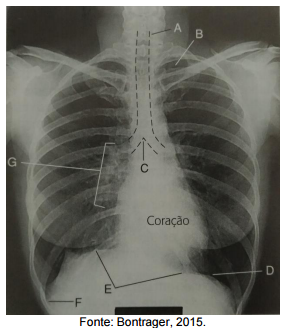

Analise a figura a seguir, que apresenta uma imagem de uma radiografia do tórax em

incidência póstero anterior.

Assinale a alternativa que apresenta a correta correlação entre a indicação e a estrutura na imagem tomográfica.